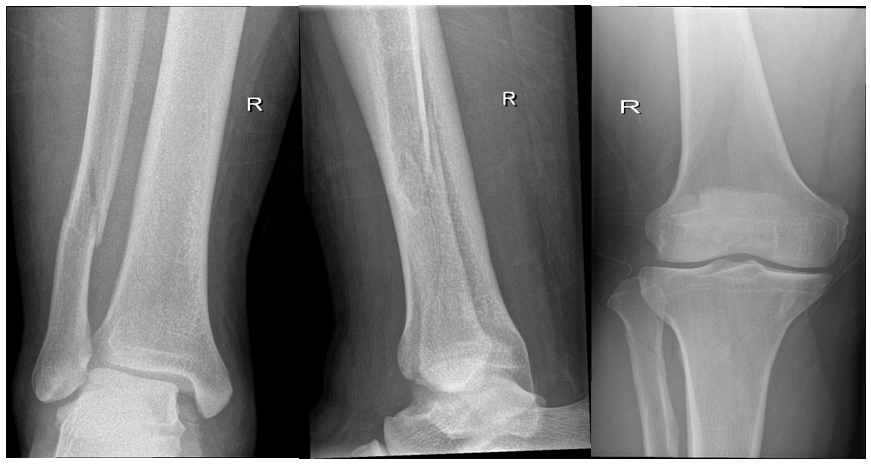

Primary right Ankle X-rays done at trauma bay (Figure 1). AP and lateral X-rays of right ankle showing after fixation (Figure 2). After 8 weeks patient underwent synedsmotic screw removal (Figure 3), and he noticed big toe deformity. At 1 year follow up patient booked for implant removal and was still complaining of same deformity and underwent FHL lengthening at same time.

Figure 1 Primary right ankle X-rays done at trauma bay.